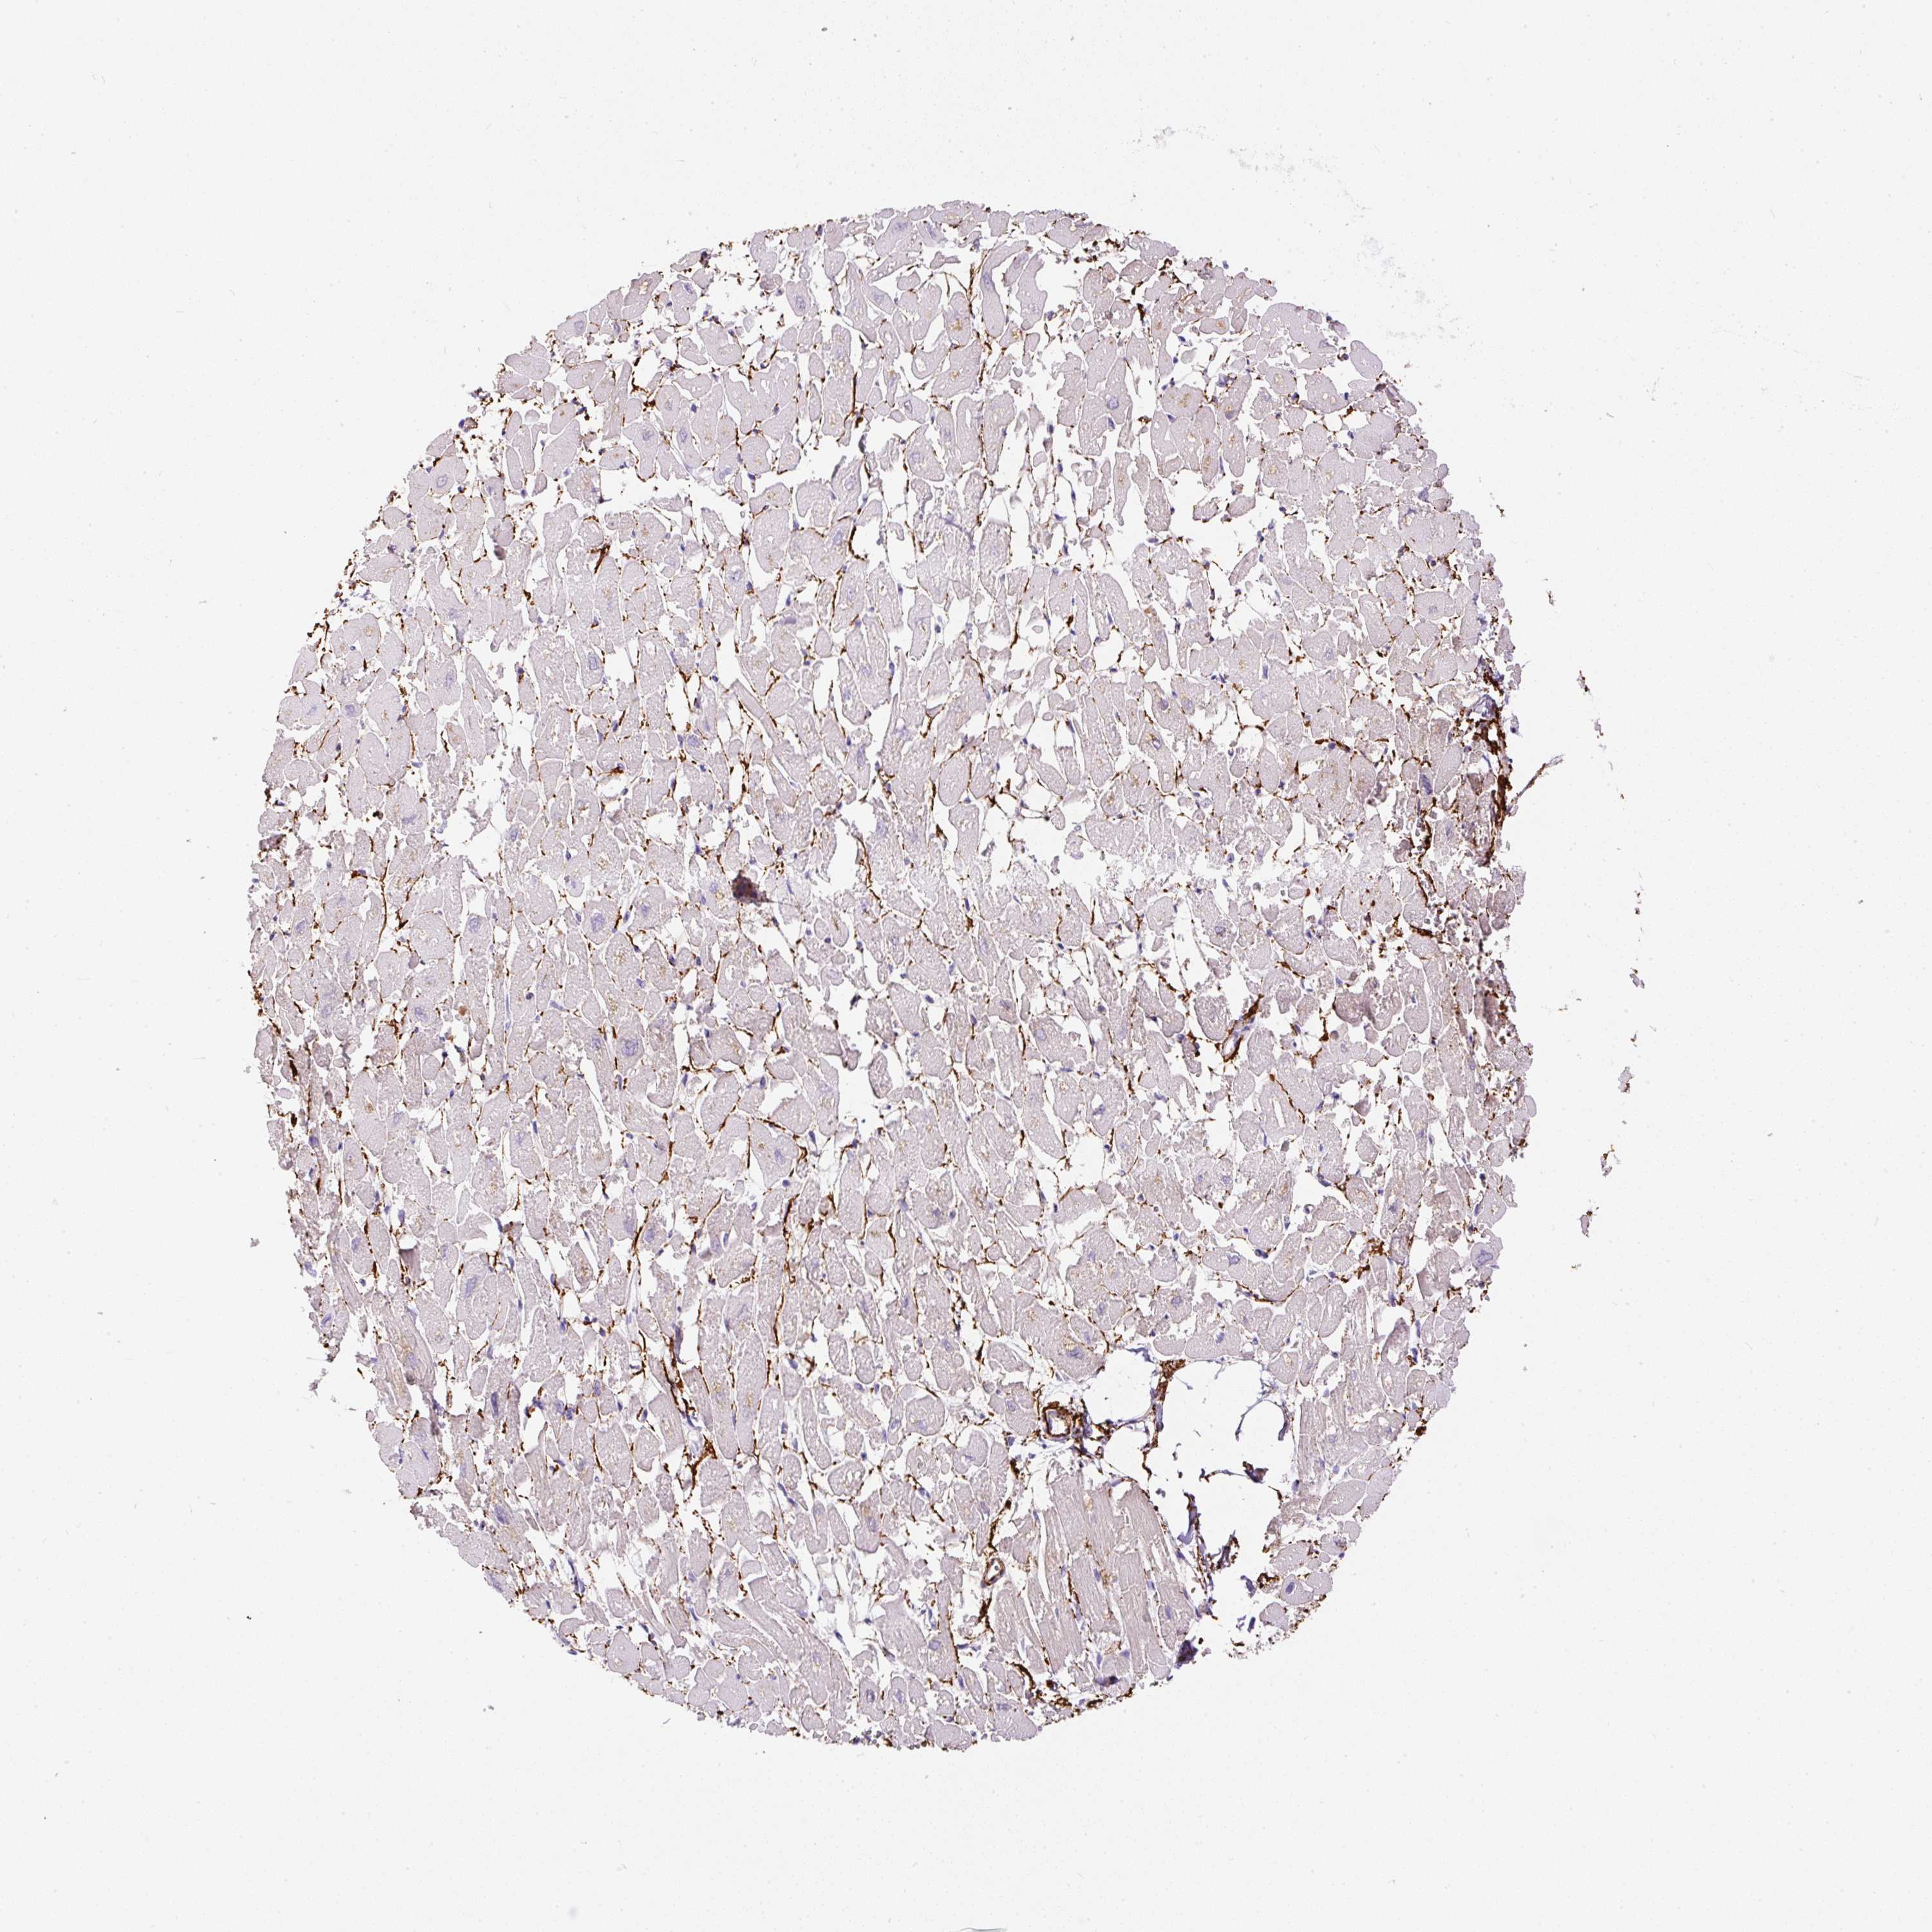

HEART MUSCLE - Antibody stainingi

Antibody staining in the annotated cell types in the current human tissue is reported as not detected, low, medium, or high, based on conventional immunohistochemistry profiling in selected tissues. This score is based on the combination of the staining intensity and fraction of stained cells.

Each image is clickable and will lead to virtual microscopy that enables deeper exploration of all samples and also displays staining intensity scores, fraction scores and subcellular localization as well as patient and tissue information for each sample.

Antibody HPA053294Antibody CAB007817

Cardiomyocytes Not detectedMedium